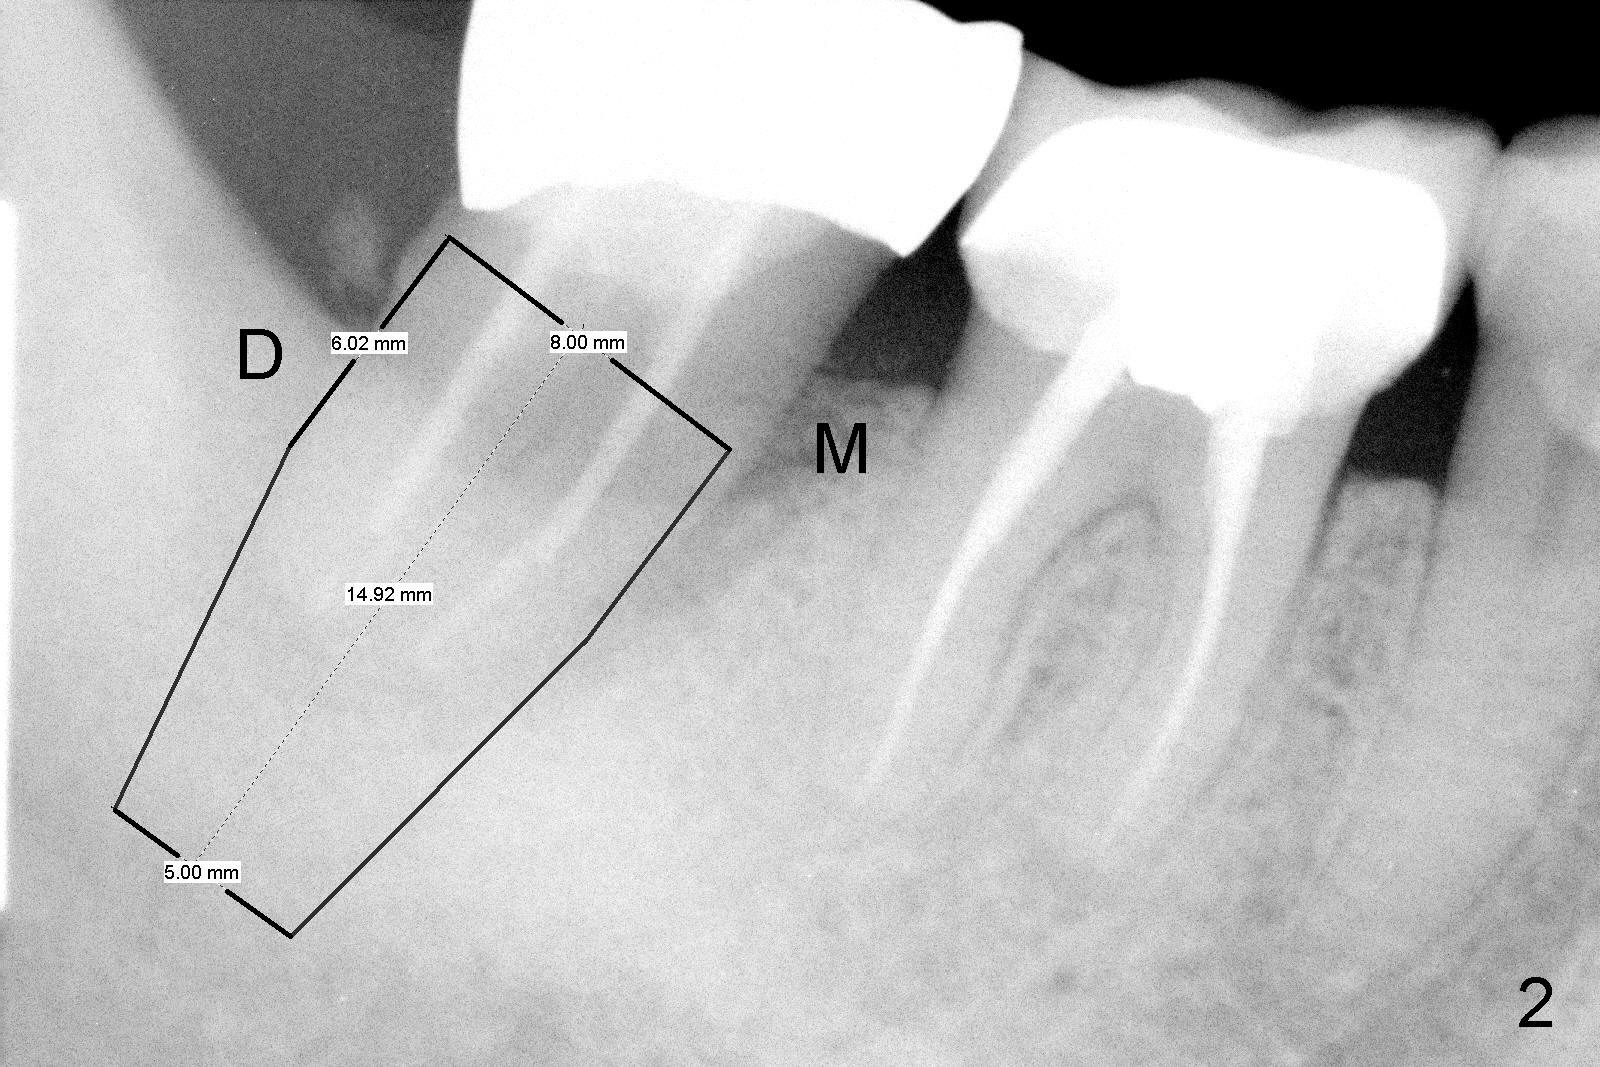

No. First at all, CT should be taken when 2D image does not show IAN. Fortunately, the surgery happens to be executed better than the plan. Clindamycin is used for socket soaking for 5 minutes. The initial osteotomy should be not exceeded 6 mm from the distal surface of the first molar (Fig.3: 5.92 mm). The 2 mm pilot drill (D) penetrates the mesial slope of the socket (red line) for 3-4 mm. There is 2.72 mm from IAN (yellow line: upper border of IAN canal). If the implant is placed along the long axis of the tooth, the initial osteotomy should start at the apex of the socket. The same pilot drill (black outline) penetrates the nascent bone for the same distance (3-4 mm) for primary stability, IAN may be invaded! The patient is a severe gagger. She manages to allow us to take this PA (Fig.3) and the next one (Fig.4 with 6x14 mm tap in place, primary stability having been achieved). To close the socket, a 7x14 mm implant is placed. Immediately postop PA is taken twice without success. The socket is closed with 2 sutures and heals around the implant 8 days postop (Fig.5,6). PA is taken 2 months postop (Fig.7). The implant is not placed as deep as planned. It is stable without paresthesia of the lower lip. An abutment is placed (Fig.8: A) nearly 3.5 months postop.